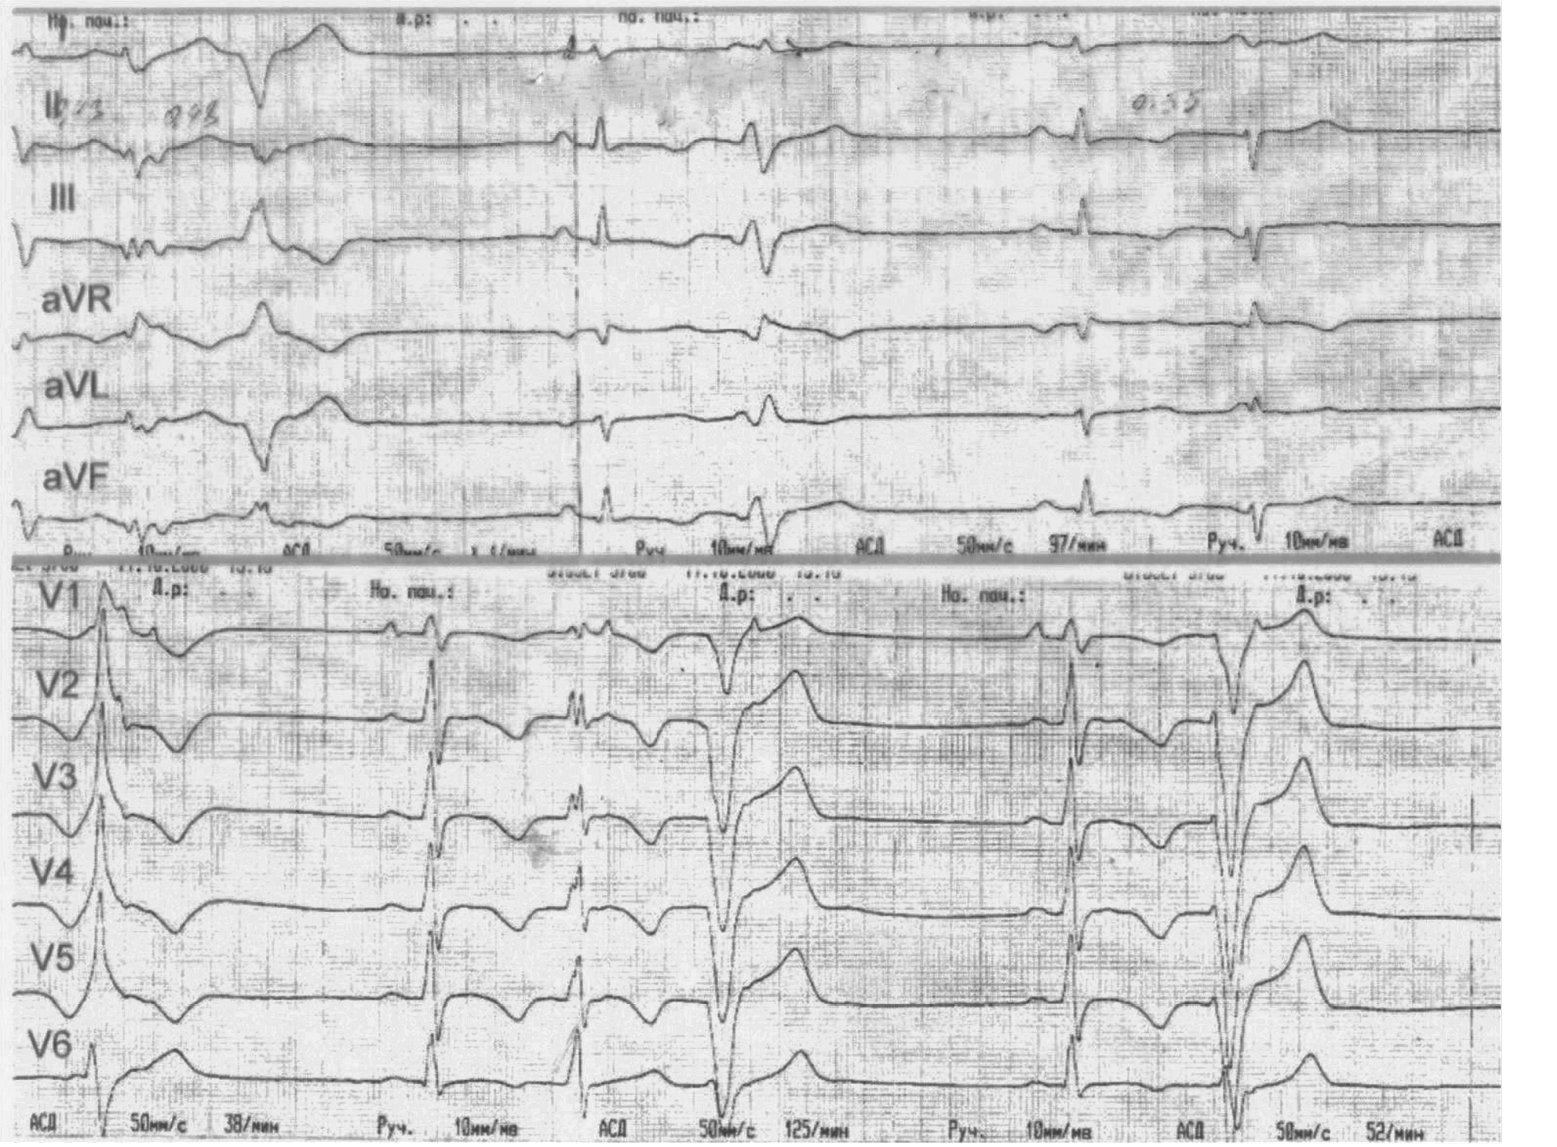

ACM is characterized by the replacement of the myocardium with fibrous and fatty tissue [27]. Currently, it is more correct to talk about ACM of both ventricles [28]. The prevalence of ACM in the population ranges from 1:1000 to 1:5000 [29]. Most often, ACM is caused by pathogenic mutations in desmosomal genes (Dsc2, desmocollin-2; Dsg2, desmoglein-2; Dsp, desmoplakin; Рkg, plakoglobin; Pkp2, plakophilin-2) and less often in nondesmosomal genes. Similar to DCM, in ACM, some mutations are associated with a high risk of developing VA at a young age [30, 31]. The diagnosis of ACM is complex and requires searching and assessing certain criteria. Although the recommendations contain a reference in Guidelines 2022 to the publication of Corrado et al. (2020) [28], the criteria for diagnosing ACM are not the 2020 Padua criteria but the previous 2010 criteria [32]. As an advantage, the Padua criteria provide an algorithm for diagnosing not only the right ventricular but also the LV process. Figure 3 presents the ECG of our 16-year-old patient with arrhythmogenic cardiomyopathy. ECG was performed during sinus rhythm. At the beginning of the recording, the moment of the cessation of unstable polymorphic VT (three complexes) was recorded. In addition, frequent polymorphic single and paired premature ventricular complexes (PVC) of the bigeminy type were noted. The major Padua criterion for the diagnosis of right ventricular ACM was identified, namely, inverted T waves in right precordial leads V1, V2, and V3 in a patient with complete pubertal development, and the absence of complete right bundle branch block. In addition, minor Padua criteria were noted for the diagnosis of LV ACM, which are inverted T waves in left precordial leads V4–V6 in the absence of complete left bundle branch (LBB) block and low-amplitude QRS (< 0.5 mV peak-to-peak) in the limb leads to the absence of obesity, emphysema, and pericardial effusion.

Fig. 3. Electrocardiogram of a patient suffering from biventricular arrhythmogenic cardiomyopathy (explanation in the text)

Рис. 3. Электрокардиограмма пациента, страдающего бивентрикулярной аритмогенной кардиомиопатией (объяснение в тексте)

Figure 4 presents the ECG of one of the patients with right ventricular ACM during classical sustained VT, which is a major criteria for diagnosing right ventricular ACM —VT with QRS morphology similar to LBB block, causing the deviation of the electrical axis to the left upward (not from the right ventricle (RV) outflow tract, the focus is located in the area of the RV free wall).

Fig. 4. Electrocardiogram of a patient suffering from right ventricular arrhythmogenic cardiomyopathy, at the time of tipical ventricular tachycardia (explanation in text)